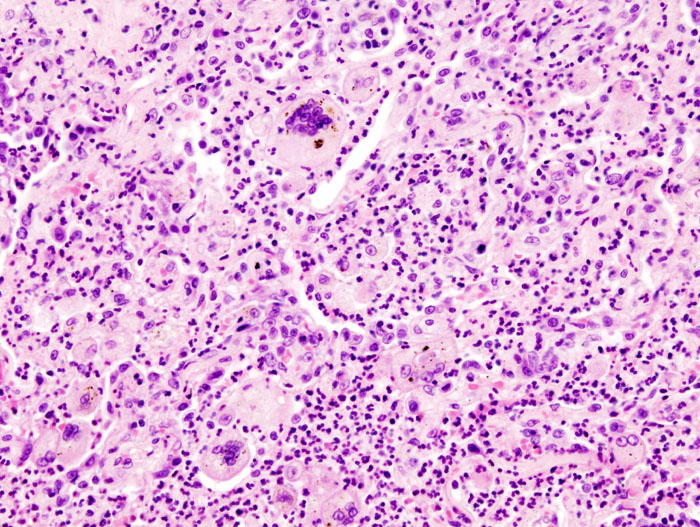

Histology of tuberculosis (TB) shows caseating granulomas, and positive acid-fast bacilli (AFB) stain.

Tuberculosis (TB) results in the hilar lymph nodes undergoing fibrosis and calcification to produce a Ghon complex as well as localized, caseating necrosis of the lung.

Tuberculosis (TB) creates a cavitary foci of caseous necrosis and has the potential to cause tuberculous bronchopneumonia or miliary pulmonary tuberculosis.